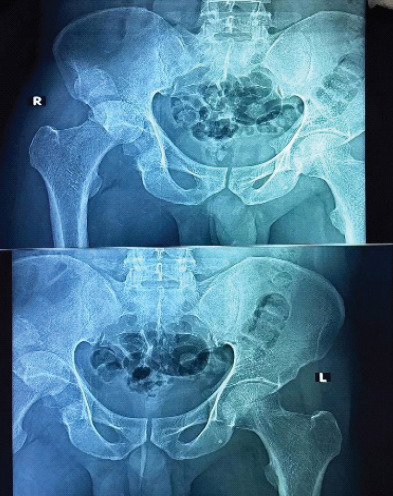

Case report: We report a case of a 42-year-old male with a chronic posterior dislocation of the right hip and a comminuted posterior wall and column acetabular fracture, presenting 2 months post-injury. The patient had previously undergone a right-sided patellectomy. Surgical intervention included THA with acetabular cage reconstruction due to segmental bone loss. At 6-month follow-up, the patient achieved pain-free ambulation, a stable prosthesis, and satisfactory functional outcomes.